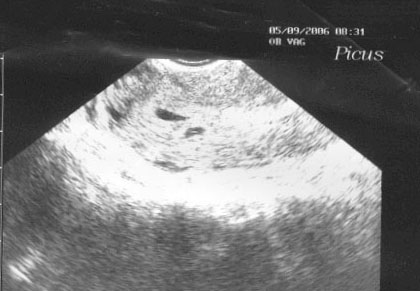

2 petezsák a 2. Uh on 5. héten

2 petezsák a 2. Uh on 5. héten